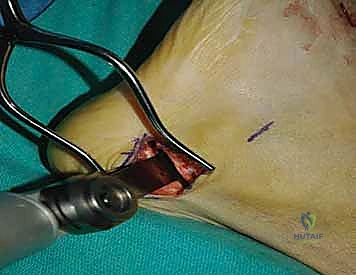

2. الشق الجراحي والوصول للمفاصل

يتم عمل شق جراحي واحد أو شقين (أحدهما في الجزء العلوي الداخلي والآخر في الجزء الخارجي) للوصول إلى مفاصل منتصف القدم دون الإضرار بالأوتار الحيوية والأعصاب والأوعية الدموية. يتم استخدام تقنيات الجراحة الدقيقة (Microsurgery) للحفاظ على الأنسجة المحيطة السليمة.

3. إزالة الغضاريف التالفة (Joint Preparation)

هذه هي الخطوة الأهم. يقوم الجراح بكحت وإزالة جميع الغضاريف المريضة والتالفة من بين العظام المراد دمجها. يجب الوصول إلى العظم الإسفنجي الصحي (Cancellous bone) الذي ينزف دماً، لأن هذا الدم يحتوي على الخلايا الجذعية وعوامل النمو الضرورية لعملية الالتحام (Fusion).